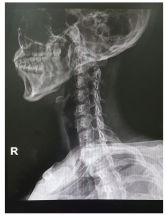

다음과 같은 자궁 경부 디스크 관련 정보에 대해 자세히 알아보십시오. B. 경추 디스크 증상, 원인 및 치료 방법. 경추추간판은 사람의 척추의 경추 또는 흉추에 위치한 추간판(보철물)이 변형되어 발생하는 질환으로 흉통, 요통 등이 발생한다. 보통은 원인불명의 자연회복을 기다리는 것이 가장 좋으며, 통증이 심한 경우에는 항염증제나 근육이완제 등을 식이보충제로 사용하기도 합니다. 압력이 심하면 수술이 필요할 수 있습니다. 예방 조치에는 좋은 자세, 체중 조절, 충분한 운동, 목과 등 근육 강화가 포함됩니다.

목디스크는 경추나 흉추에 있는 디스크(보철물)의 변형으로 인해 발생하는 질환으로 다음과 같은 증상이 나타날 수 있습니다.

목의 추간판 탈출증은 다음과 같은 원인으로 인해 변형된 디스크(의치)로 인해 발생하는 상태입니다.